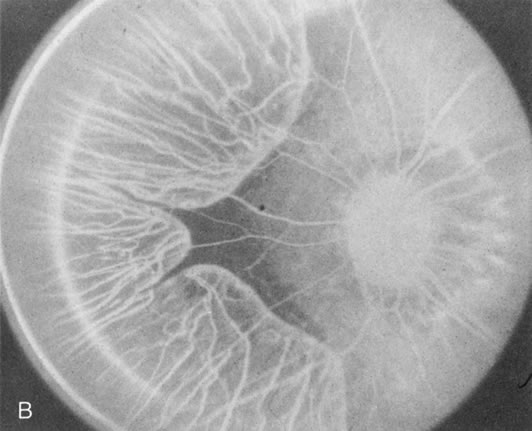

When the macula has typical superficial linear plications radiating from the fovea seen with schisis (e.g., juvenile retinoschisis, Goldmann-Favre disease), FA is normal (Fig. 8A and B). This indicates that the pathology is in the inner retina (probably Henle's fiber layer, considering the spokewheel pattern). However, when the schisis flattens, it is not uncommon to see a transmitted hyperfluorescence suggesting a secondary atrophy to the RPE (Fig. 8C and D).

Fig. 8. Juvenile XLR retinoschisis. The superficial macula schisis (A) does not affect the angiogram (B) except in a few areas where it has flattened and resulted in some pigment dispersion. When the macular schisis has entirely flattened (C) there is a mild transmission hyperfluorescence (D). At this stage the diagnosis can be suspected by the presence of an inferior retinoschisis (present in half) and confirmed by the typical electroretinographic finding of a scotopic electronegative response (present in all affected males).